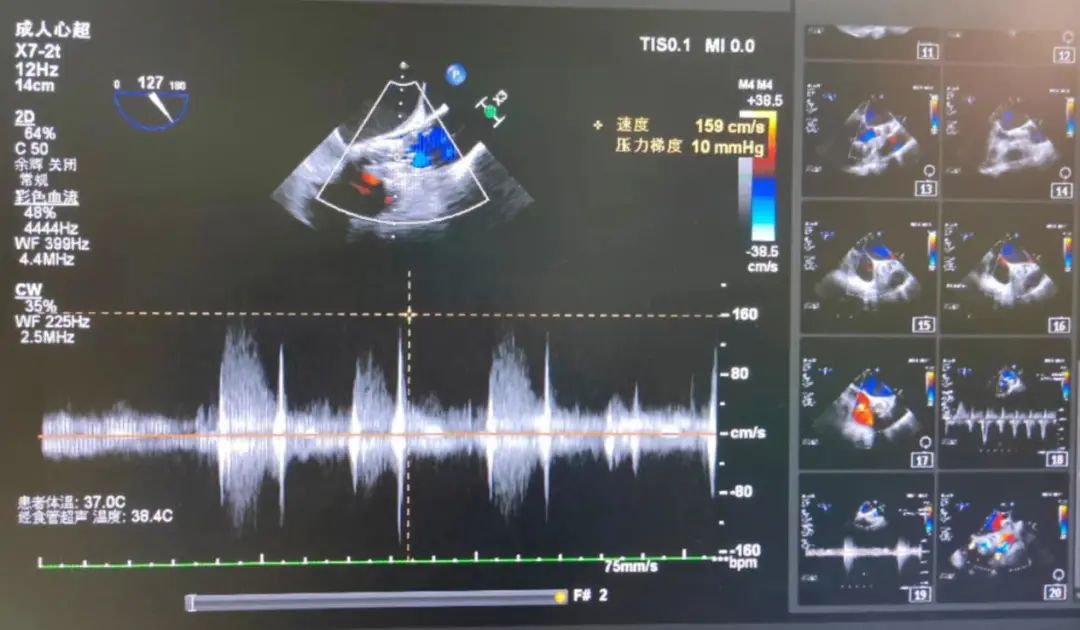

释放后无瓣周漏,微量反流

术后平均压差在10mmHg左右,从重度反流变为微量反流,瓣膜正常工作。